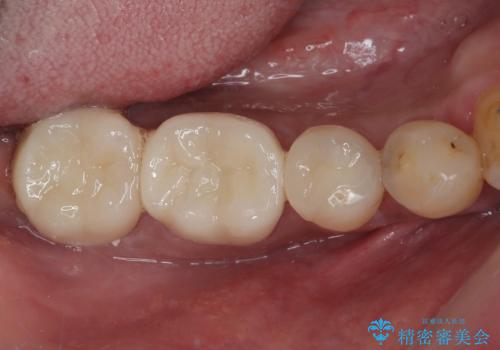

銀歯をセラミックにしたい オールセラミッククラウン

担当医 有澤哲郎